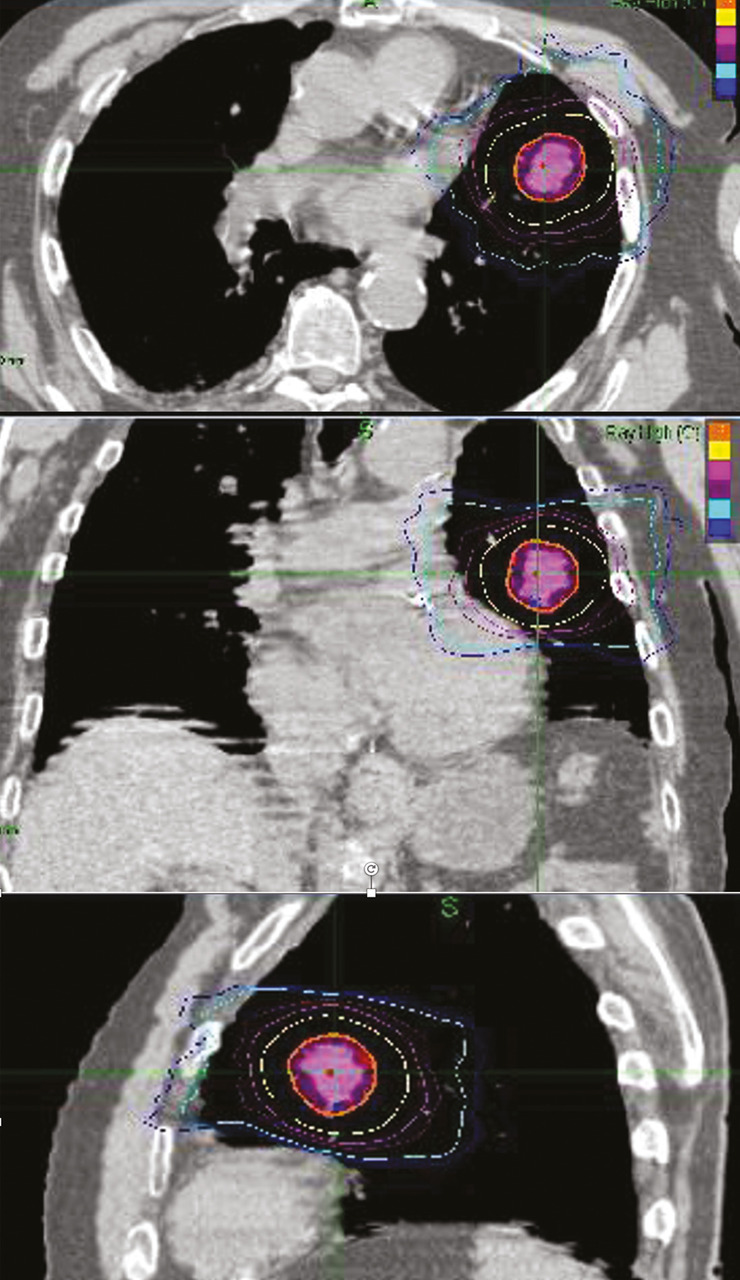

La radiothérapie en conditions stéréotaxiques (SBRT) consiste à délivrer une forte dose d’irradiation en moins de dix séances avec une haute précision dans un volume cible restreint (lésion de moins de 5 cm et pas plus de trois lésions synchrones).16 C’est une technique de haute précision demandant une expertise et un équipement particulier au sein des départements de radiothérapie. Elle peut être réalisée sur un accélérateur classique mais adaptée aux conditions stéréotaxiques ou sur un appareil dédié (Cyberknife  ; fig. 3). Elle n’est pas encore disponible dans toutes les indications dans tous les centres. Ainsi, il faut tenir compte de l’accessibilité au centre de traitement, qui peut nécessiter quelques aménagements logistiques pour les patients les plus âgés ou les plus dépendants. Cependant, le faible nombre de séances en fait un traitement particulièrement attractif chez le sujet âgé, même si la durée de la séance peut être plus longue et l’implantation de fiduciels parfois indispensable. Elle est une alternative à la chirurgie pour les cancers bronchiques non à petites cellules T1 -T2N0M0.17 Elle est aussi particulièrement utile dans la prise en charge des métastases cérébrales en limitant les altérations cognitives en comparaison de l’irradiation de l’encéphale en totalité, quel que soit l’âge. Elle se développe significativement dans les cancers de la prostate localisés de faible risque et dans les cancers du rein. Cependant, peu de données sont actuellement disponibles concernant la toxicité tardive et la qualité de vie chez les patients très âgés traités par SBRT.